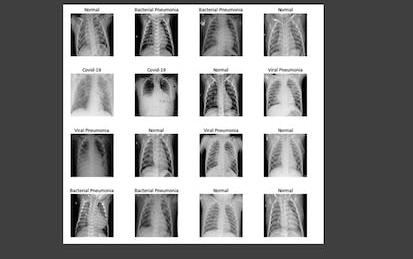

AI-Powered Chest Disease Detection and Classification

Hello everyone and welcome to this hands-on guided project on Artificial intelligence (AI)-powered chest disease detection and classification.